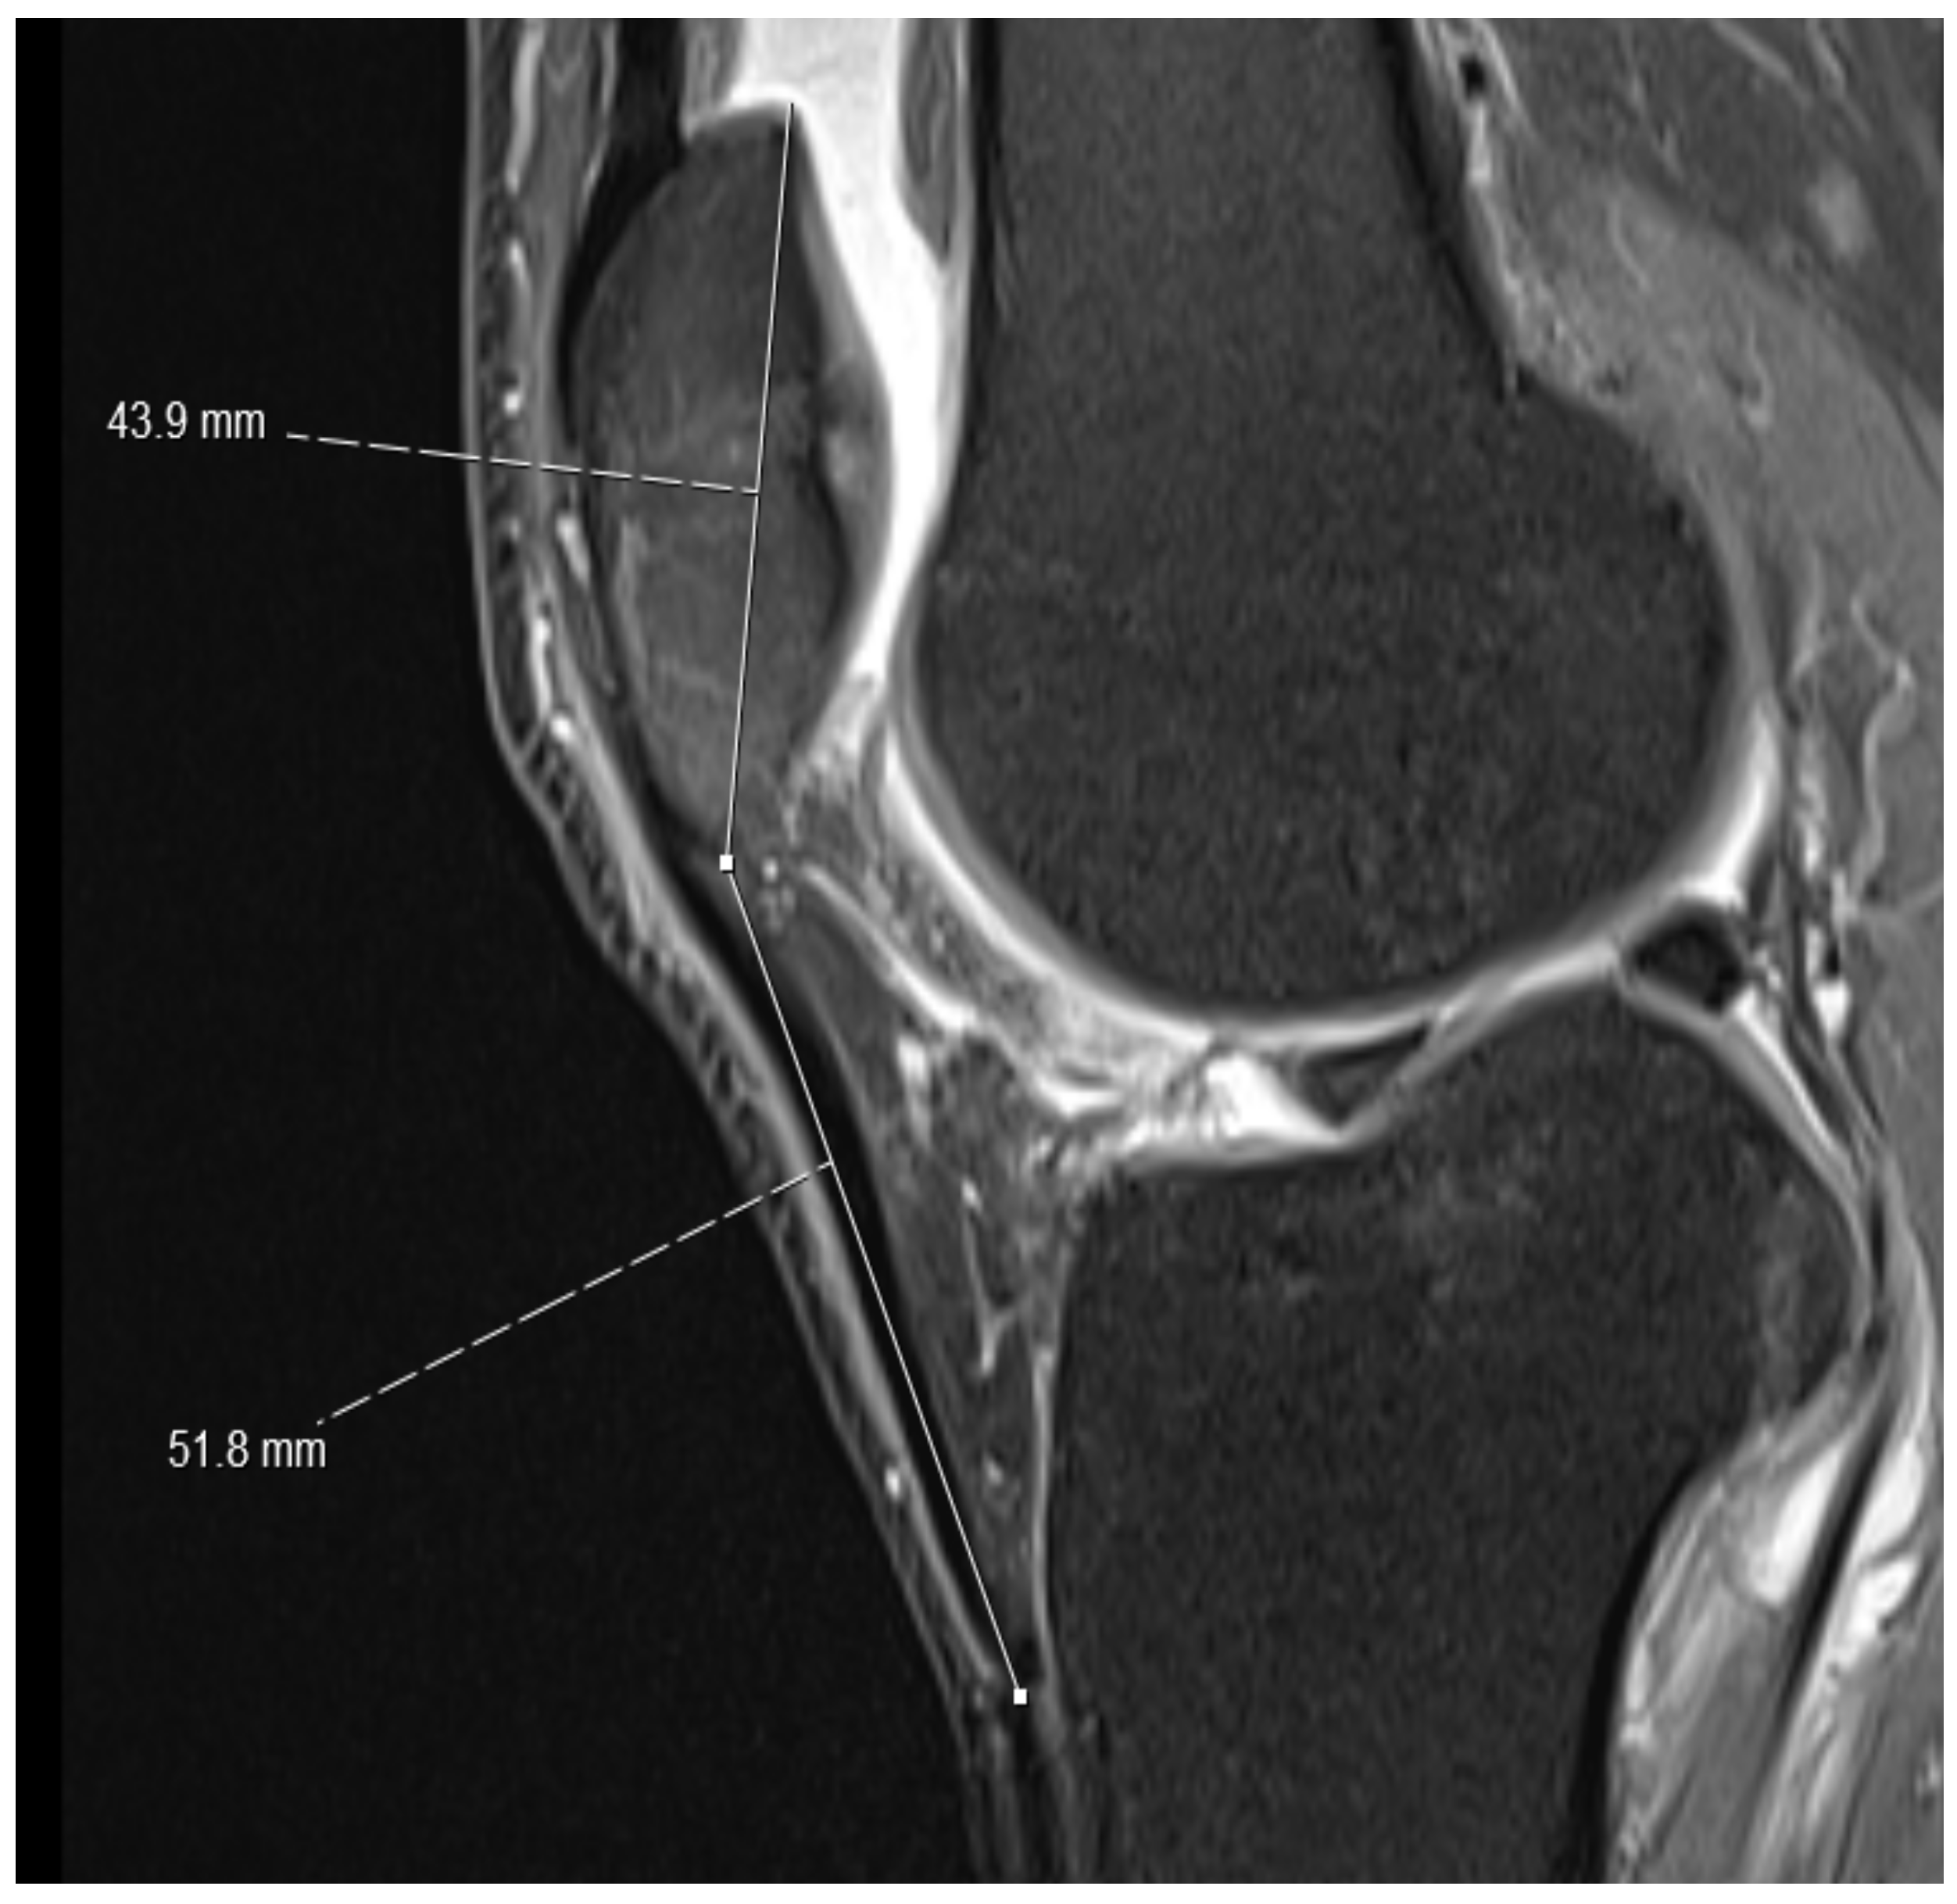

- On the sagittal PD-weighted images, the patellar ligament and the max. pole to pole distance in the patella were measured to calculate the Insall-Salvati index (Figure 1).

Figure 1. Normal Insall-Salvati index. For the knee in the figure, an Insall Salvati index of 1.18 was obtained by dividing the length of the patellar ligament (51.8 mm) by the patellar pole distance (43.9 mm). - (2)